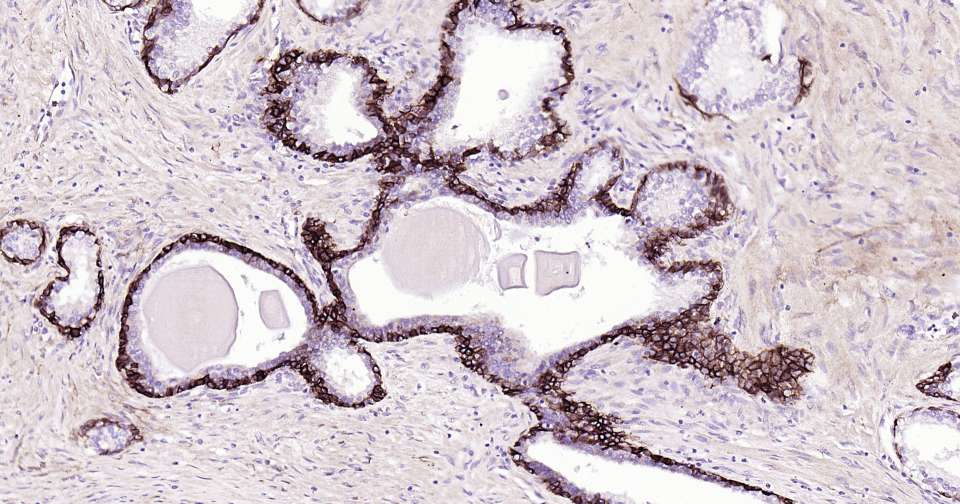

Immunohistochemical analysis of paraffin embedded human prostate tumor tissue slide using IHC0376H (Human NGFR/p75NTR Kit).